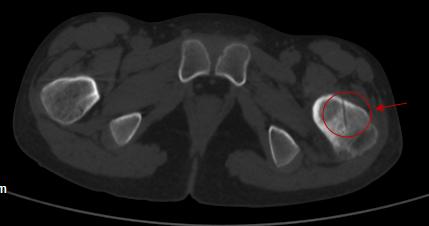

近期,邓某某疼痛明显加重到我院就医,检查结果提示左侧股骨颈肿瘤样病变。

我院术前图片

由于邓某某年龄较小,骨骺未愈合,手术难度大,如若进行切开手术治疗,手术创伤较大,还不一定能找到肿瘤。同时,邓某某左侧股骨颈肿瘤位置距离骨骺线较近,若不能精准定位,极易破坏骨骺线,导致患肢停止生长。对于肿瘤侵犯左侧股骨颈,肿瘤继续生长危害极大,肿瘤切除仍然是治疗的关键。考虑到患者的实际情况,与家属沟通后,在华西段宏教授指导下我科为患者成功进行了国内首例AR辅助股骨颈肿瘤精准治疗手术。